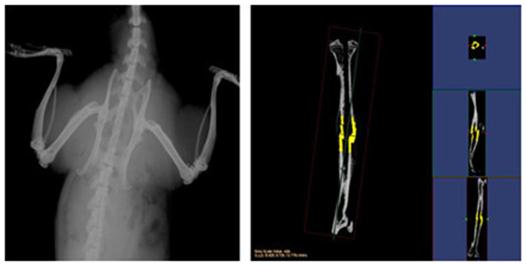

小动物CT

小动物CT服务通过采用锥形X线束,不仅能够获得真正各向同性的容积图像,提高空间分辨率,提高射线利用率,而且在采集相同3D图像时速度远远快于扇形束CT。可以对不脱钙骨骼和动物牙齿进行microCT检测服务,分析其内部结构和提供给您高清晰、高质量的扫描图像。活体研究对象通常为小鼠、大鼠或兔等活体小动物,可以实现生理代谢功能的纵向研究,显著减少动物试验所需的动物数量;离体研究对象通常为离体标本(例如骨骼、牙齿)或各种材质的样品,可分析其内部结构和力学特性。

结果示意图: